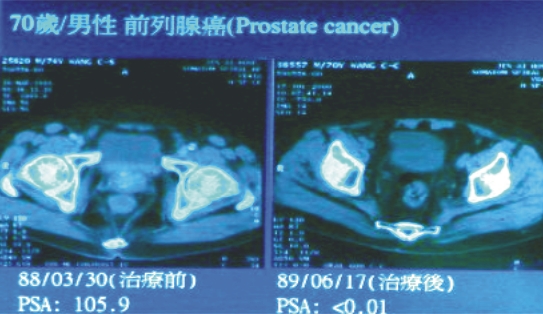

(一) 前列腺癌:

25例患者(其中第I期10例,第II期14例,第III期5例),只接受過切片或經尿道前列腺刮除術等保守治療,而以”遠隔放射線治療”為主要治療方式;並以”三度空間順形治療”為追加局部治療之方法。平均追蹤時間為2年,90﹪的患者治療六個月後腫瘤指數(PSA)<0.01,100﹪於一年後<0.01,且只有1例於治療中曾出現短暫血尿,其餘均完全無副作用,且目前控制率100﹪,尚無病患復發。

|

|